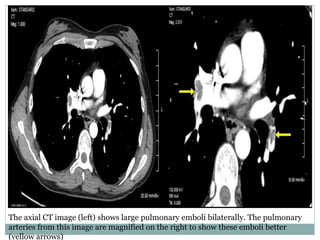

The axial CT image (left) shows large pulmonary emboli bilaterally. The pulmonary

arteries from this image are magnified on the right to show these emboli better

(yellow arrows)

The axial CTimage (left) shows large pulmonary emboli bilaterally. The pulmonary arteries from this image are magnified on the right to show these emboli better (yellow arrows)